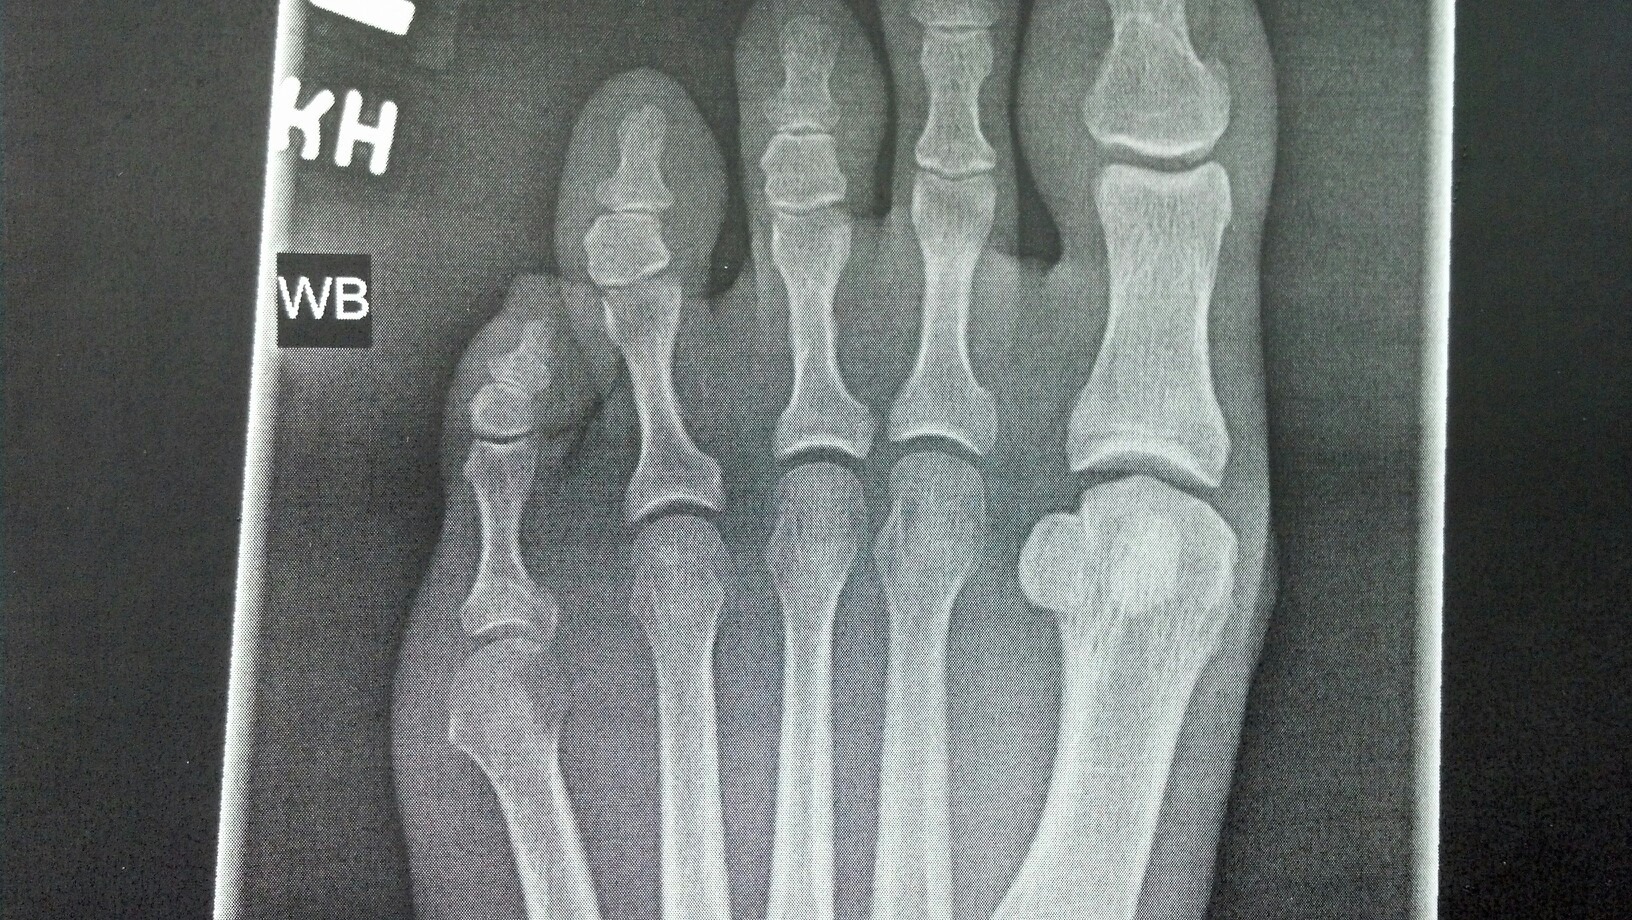

They took xrays of my left foot in various positions and long story short, no former fracture, I just have the beginning of a bunion. I always thought a bunion was a big protruding bump on the side of your foot, but instead I learned that a bunion is actually a “hallux abducto valgus deformity” where the bones connected to your big toe are simply out of alignment with the rest of your toes.

Here’s my xray:

After reviewing the xray the doctor was surprised I’m not having any pain at my pinky-toe area since those bones are really out of alignment and look like they are rubbing. The only pain I have is between my big toe and second toe and it’s not all the time, just after a lot of activity or heavy walking or running around barefoot or in flip flops for too long. He said the pain I feel is from the joint becoming inflamed due to rubbing because of the misalignment. He said it’ll never get better, but could likely just stay as-is (or get worse) and that I just need to keep doing whatever it is that I do that seems to help alleviate symptoms when they appear (which is typically ibuprofen, ice, and wearing my heels or wedges).

I was expecting to hear about how wearing heels or wedges are BAD, but instead he said that my stiff soled shoes are the perfect choice for alleviating the pain because that style of shoe takes all the pressure off my toe joint since the sole isn’t flexible. He also said to prevent flare-ups I should wear shoes as much as possible and limit my barefoot time (um, hard to do when I’m home all day).

Did you know there’s little “kneecaps” on the bottom of your big toe joint as well? That’s what those two little round bones are- sesamoid bones!